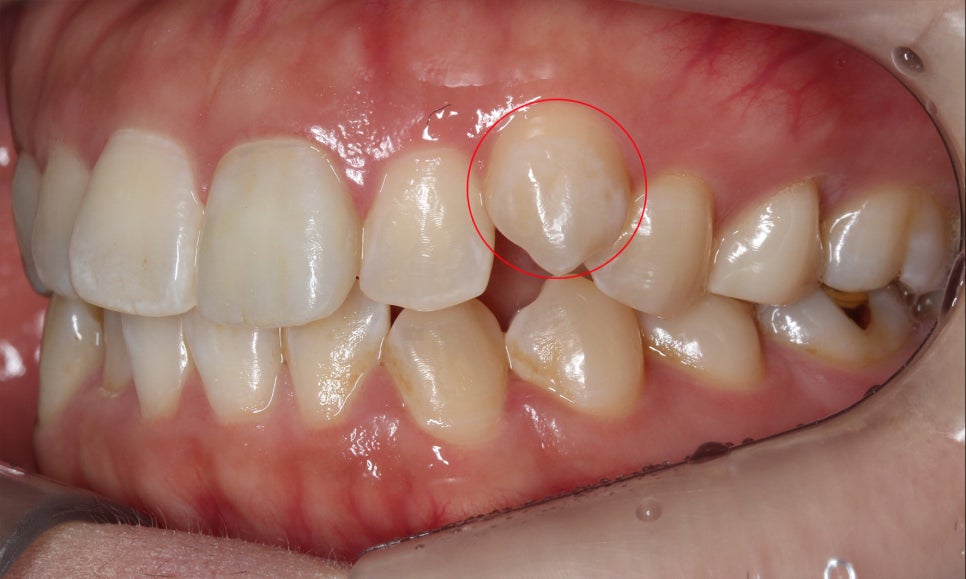

송곳니교정 후 교합평면 사진을 보면

송곳니가 변위된 모습을 확연하게

확인할 수 있는 모습으로 표시된 부분의

잇몸 라인이 수평적으로 균일하게

바뀐 모습입니다.